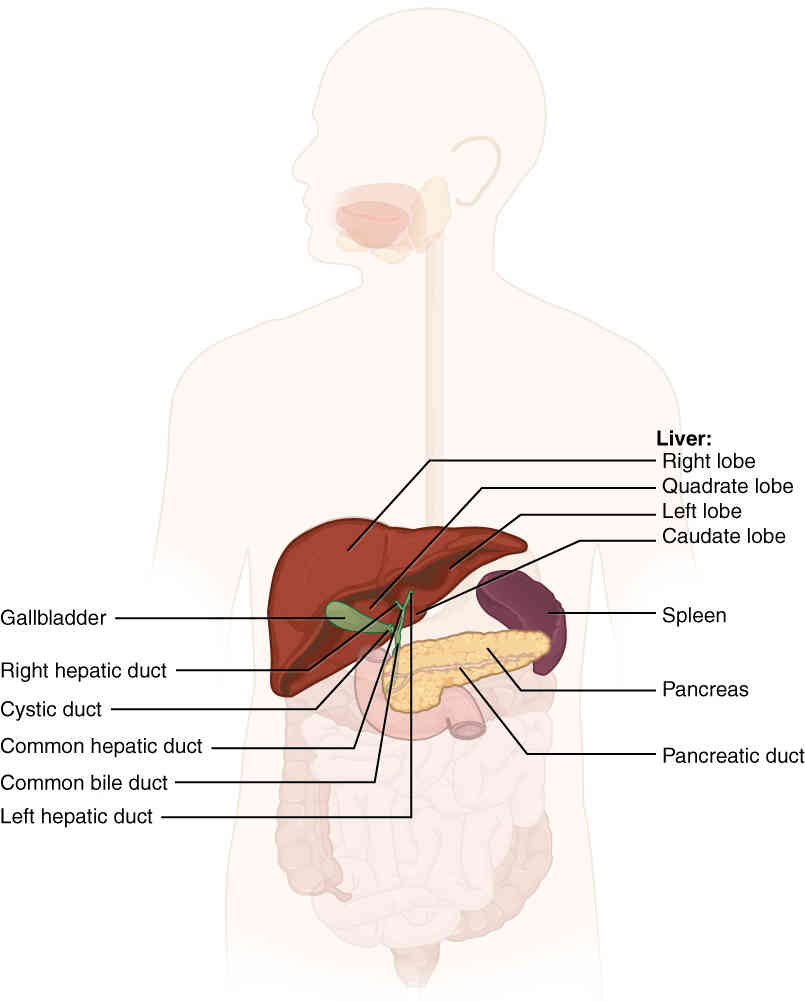

This page is under construction. For now, it is just a resource of the images found in the OpenStax Anatomy and Physiology Handbook. It wil slowly change into a revision tool. Each slide has a number. Use this to refer to the slide. When completed, it will have an unlabelled section, with labelled slides in parallel. On the unlabelled slides, write your answer and use the labelled slide to assess yourself. Keep track by also noting the number on each slide. Improvement at each attempt is important, more so than full marks on a first attempt.